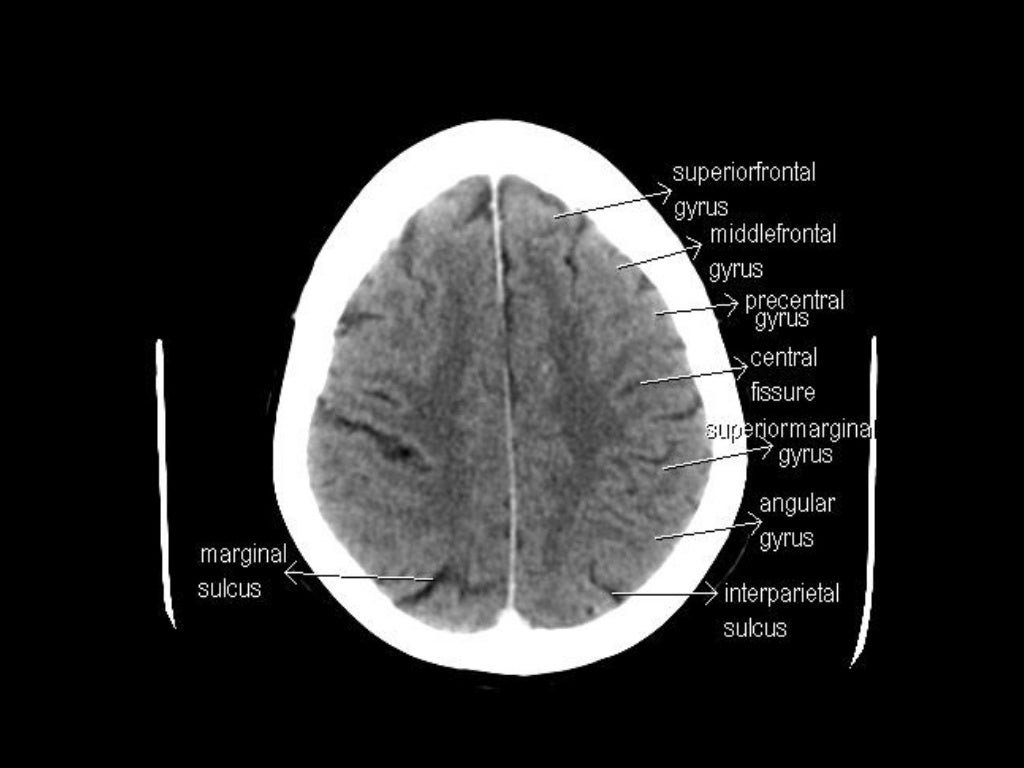

Ct Anatomy Study . It is performed with a higher radiation dose and larger dose of iv contrast, which helps to evaluate subtle areas of bowel inflammation. To get the full picture of abdominal anatomy, the examiner needs to move through the slices from cranial (proximal) to caudal (distal) while examining structures from their beginning. Radiological anatomy is where your human anatomy knowledge meets clinical practice. This case is used in 82. Explore detailed anatomical views and multiple modalities (over 8,900 anatomic structures and more than 870,000 translated. But instead of creating a flat, 2d image, a ct. What is a ct scan? Computed tomography (ct) scans are an extremely common imaging modality. A ct (computed tomography) scan is a type of imaging test. In this article, we will outline the basic principles. Annotated teaching ct head in standard and bone windows. This article lists a series of labeled imaging anatomy cases by body region and modality. Normal ct head with annotated and original images.

In this article, we will outline the basic principles. Radiological anatomy is where your human anatomy knowledge meets clinical practice. This case is used in 82. This article lists a series of labeled imaging anatomy cases by body region and modality. Annotated teaching ct head in standard and bone windows. Explore detailed anatomical views and multiple modalities (over 8,900 anatomic structures and more than 870,000 translated. Normal ct head with annotated and original images. A ct (computed tomography) scan is a type of imaging test. Computed tomography (ct) scans are an extremely common imaging modality. It is performed with a higher radiation dose and larger dose of iv contrast, which helps to evaluate subtle areas of bowel inflammation.